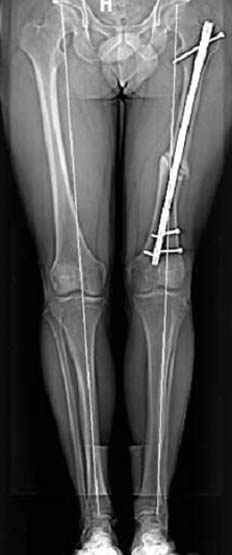

Несколько снимков из моей коллекции, чтобы разьяснить, почему мы до сих пор делаем различные варианты остеотомии.

N3 рисунок окончательный снимок, после операции моя рентгенограмма должен выглядеть примерно как эта картина. На N4 снимке клин перед удалением; N5 послеоперации 3 нед.; N6 окончательная рентгенограмма.

Отправитель: Djoldas Kuldjanov 23 Ноябрь 2004, 18:21

пластическая модель; и коррекция бедра аппаратом Илизарова.